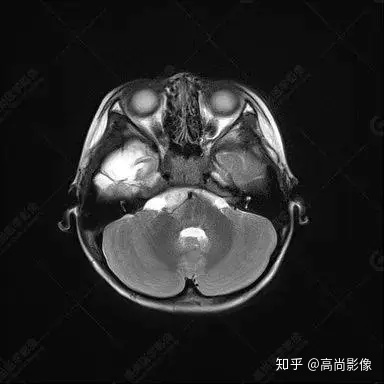

右側(cè)顳葉腫瘤切除術(shù)后(具體不詳):右側(cè)顳部骨質(zhì)不連續(xù)呈術(shù)后改變,右側(cè)顳葉術(shù)區(qū)見片狀長T1長T2信號影,F(xiàn)LAIR呈低信號;術(shù)區(qū)后方右側(cè)顳枕葉見一巨大占位性病變影,邊界欠清,大小約6.2×5.8×4.3cm(前后×左右×上下),信號不均勻,T1WI呈等稍低信號間雜少許高信號,T2WI呈高稍低混雜信號,DWI示部分病灶彌散受限,相應(yīng)ADC圖減低,磁敏感序列見部分呈極低信號,增強(qiáng)掃描可見明顯不均勻強(qiáng)化,鄰近硬腦膜及小腦幕增厚并明顯強(qiáng)化;另延髓右前方及右側(cè)橋小腦角區(qū)見一不規(guī)則形異常信號影,大小約3.2×1.3×3.7cm(左右×前后×上下),呈長T1稍長T2信號,F(xiàn)LAIR呈等信號,DWI未見受限,增強(qiáng)后明顯均勻強(qiáng)化,鄰近腦膜明顯強(qiáng)化。鄰近腦實質(zhì)及右側(cè)顳角明顯受壓;左側(cè)大腦半球未見局灶性信號異常,中線結(jié)構(gòu)稍左移。

右側(cè)顳葉腫瘤切除術(shù)后:現(xiàn)術(shù)區(qū)后方右側(cè)顳枕葉及延髓右前方占位,右側(cè)顳枕部硬腦膜及小腦幕明顯強(qiáng)化,結(jié)合既往影像資料,考慮為胚胎源性惡性腫瘤,如非典型畸胎樣/橫紋肌樣瘤(AT/RT)或原始神經(jīng)外胚層腫瘤(PNET)。

術(shù)后隨訪病理結(jié)果:非典型畸胎樣/橫紋肌樣瘤。